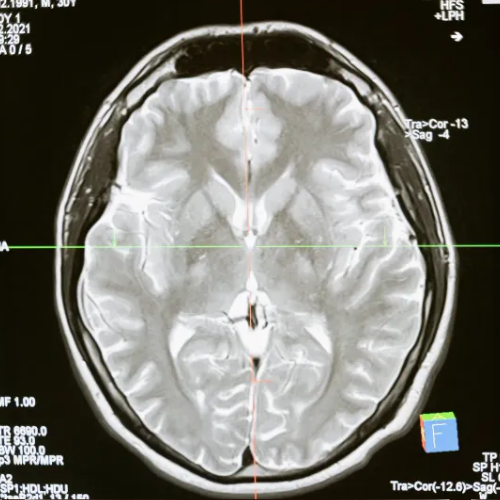

병원을 찾아 뇌 MRI, CT 등 여러 검사를 받아도 특별한 이상이 발견되지 않는 경우가 많고, 이로 인해 원인을 알지 못한 채 고통받는 환자들도 적지 않습니다.

이는 어지럼증의 원인을 주로 뇌나 귀의 구조적 문제에만 초점을 맞춰 진단하기 때문입니다.

Q1. "MRI상으로는 이상이 없는데, 왜 계속 어지러울까요?"

구조는 정상이지만 기능적으로는 불안정한 경우가 있습니다.

두개경추(머리와 목을 연결하는 부위)는 작은 틀어짐만으로도 전정신경계나 자율신경계에 영향을 줄 수 있으며, 이로 인해 어지럼증, 두통, 불안감 등이 반복될 수 있습니다.

두개경추(머리와 목을 연결하는 부위)는 작은 틀어짐만으로도 전정신경계나 자율신경계에

영향을 줄 수 있으며, 이로 인해 어지럼증, 두통, 불안감 등이 반복될 수 있습니다.